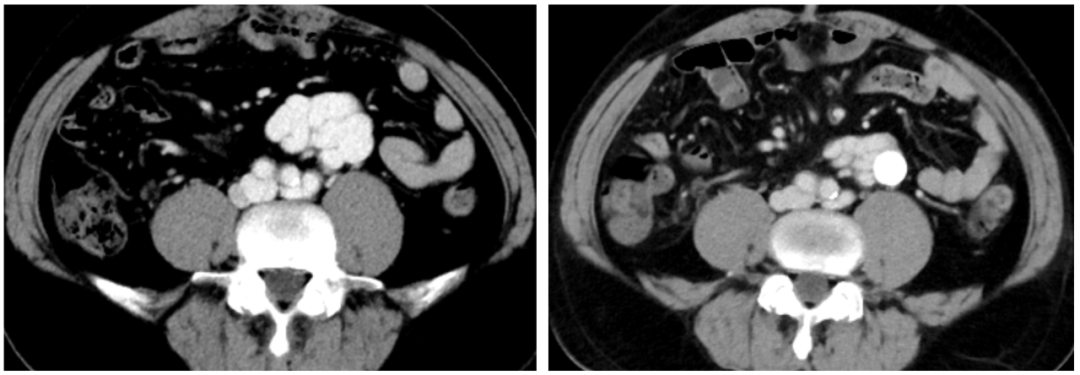

2023-08-10 多排CT全腹部直接增强:肝硬化,脾大,门静脉纤细,食管胃底静脉曲张、异常分流道(肠系膜下静脉-下腔静脉分流,引流端近下腔静脉肾静脉分叉处)

2)腹部增强CT

异常分流道曲张静脉较前显著萎缩

术后患者的肝脏血管超声提示患者原本的离肝血流已逆转为向肝血流,1月后的CT复查显示门静脉较术前的纤细状态已得到明显恢复,间接证实TIPS分流并未进一步降低患者的肝脏灌注,其随访至今也未在发生肝性脑病。对于自发性门体分流所致的反复肝性脑病患者,相信TIPS+异常分流道近端栓塞是值得进一步探索研究的治疗方法。需临床进一步验证。